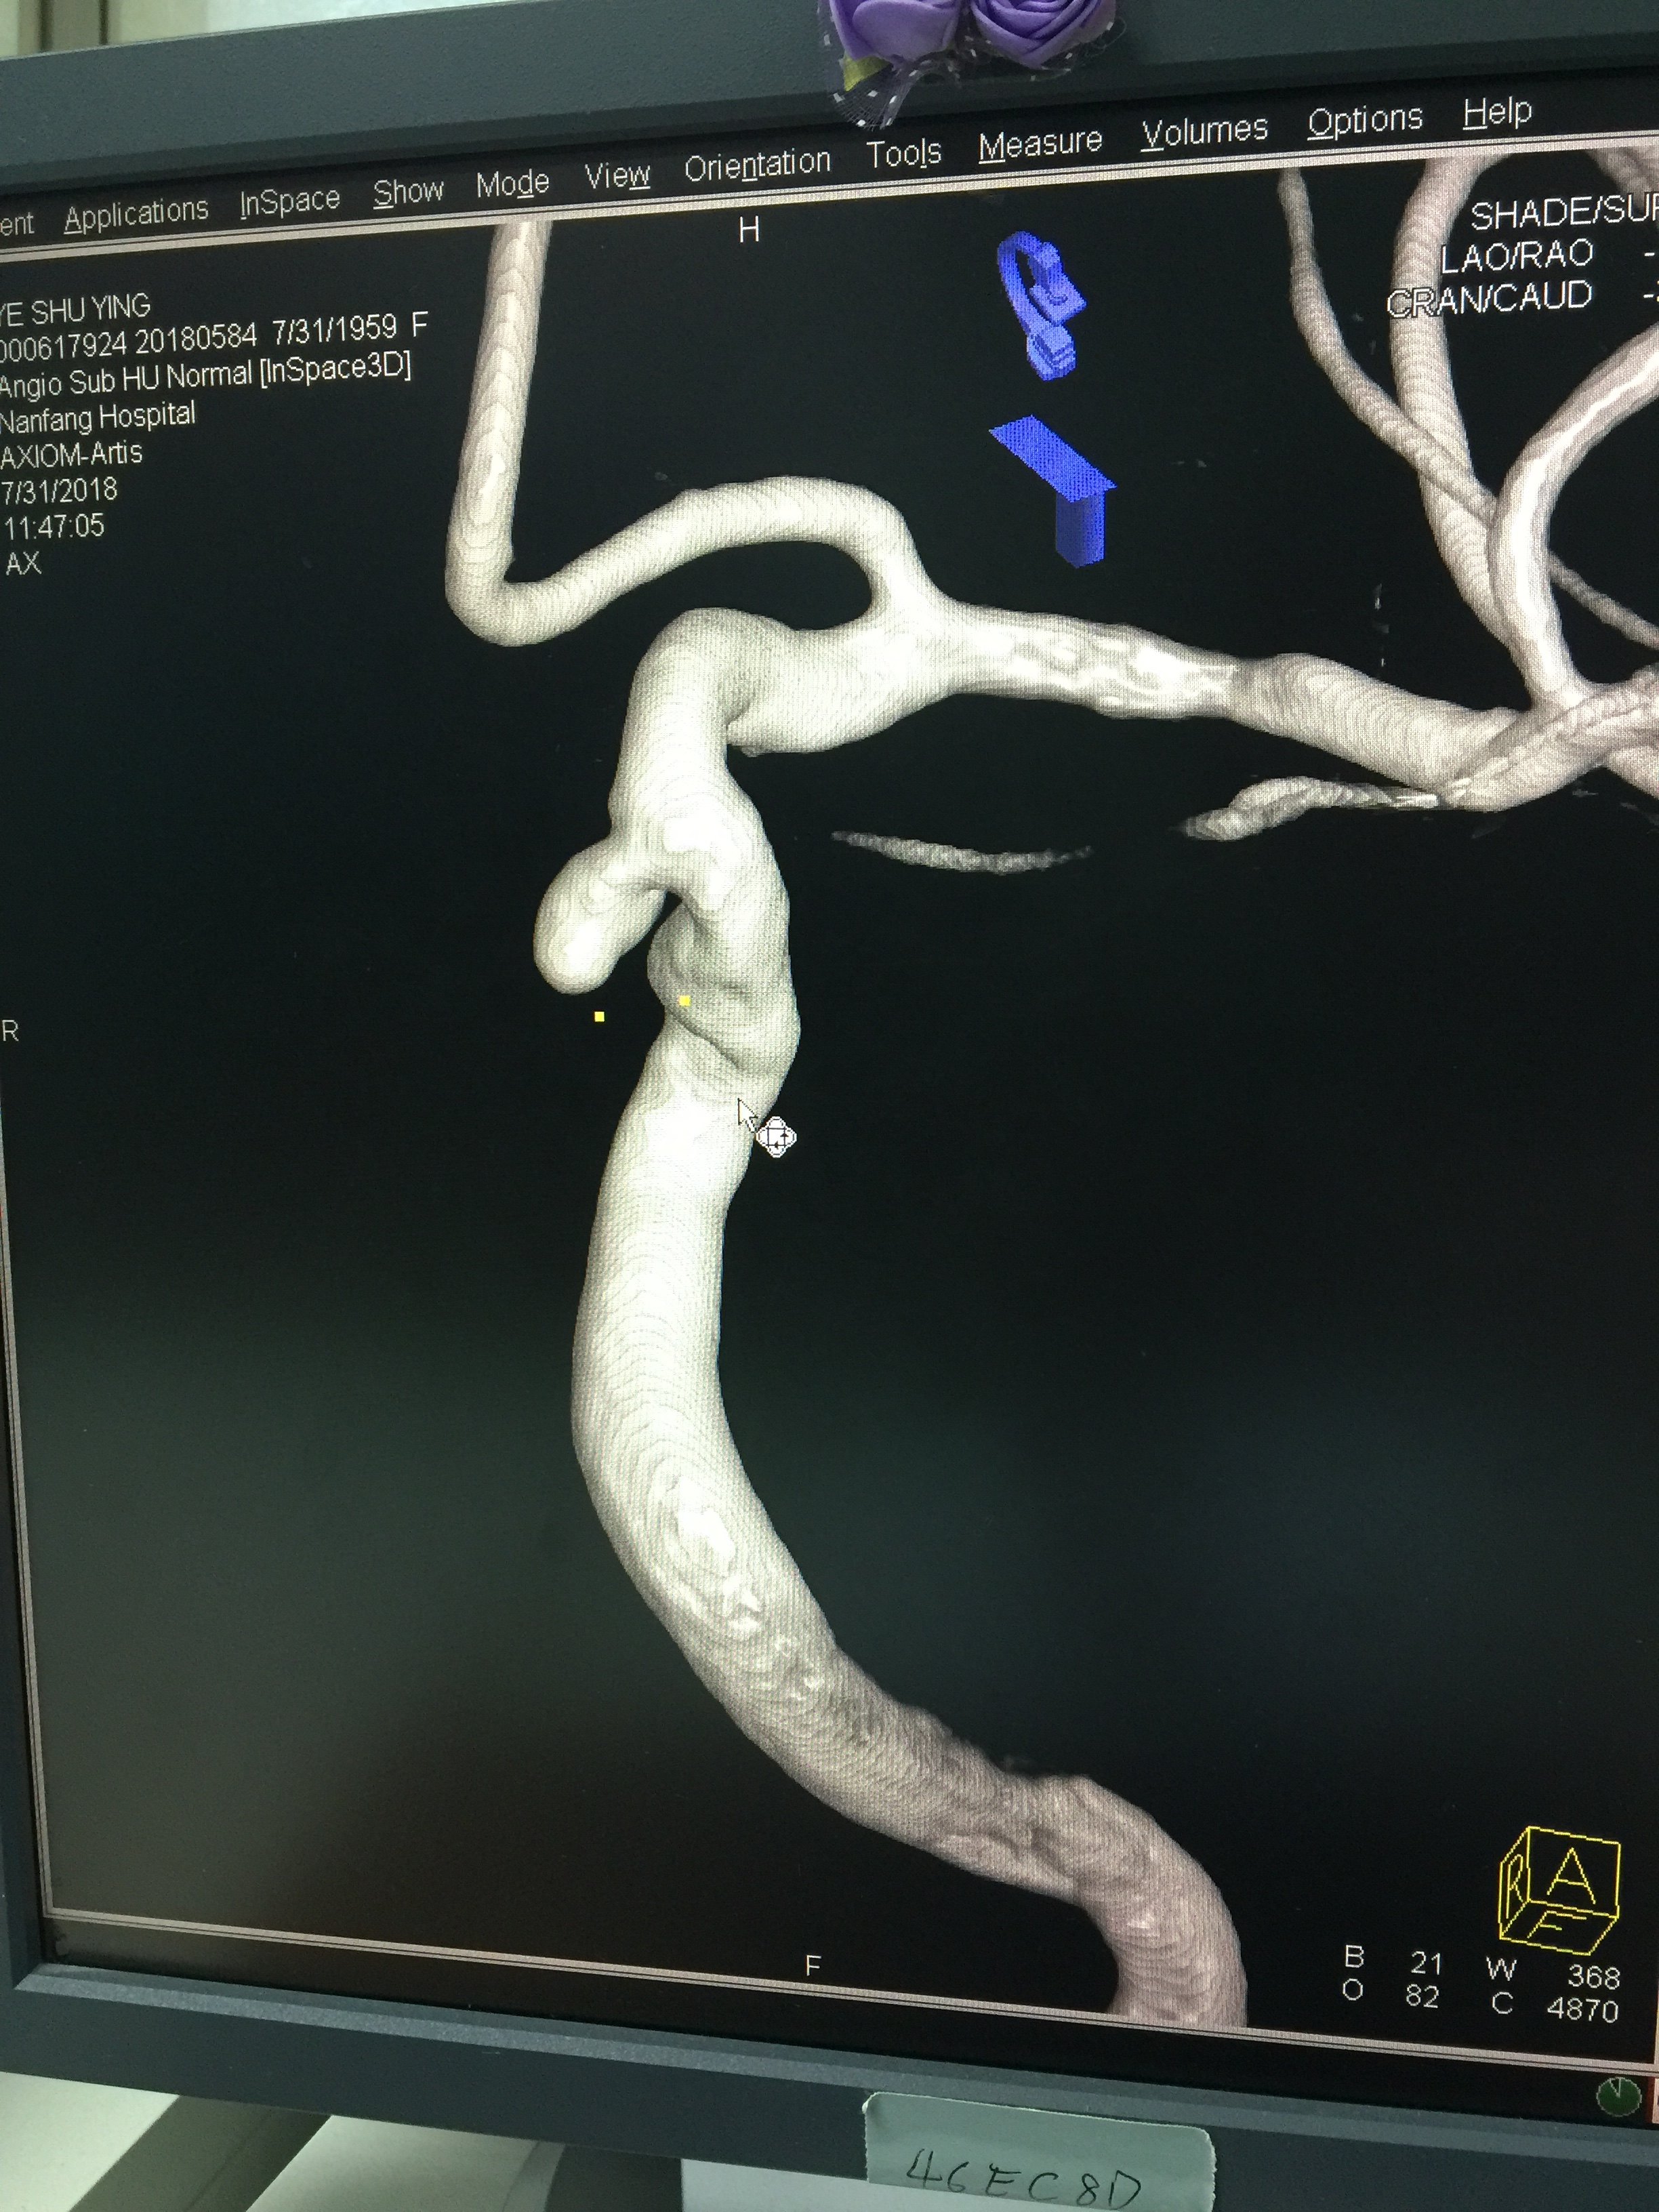

病例二:前交通动脉瘤-术前

1534032328.png